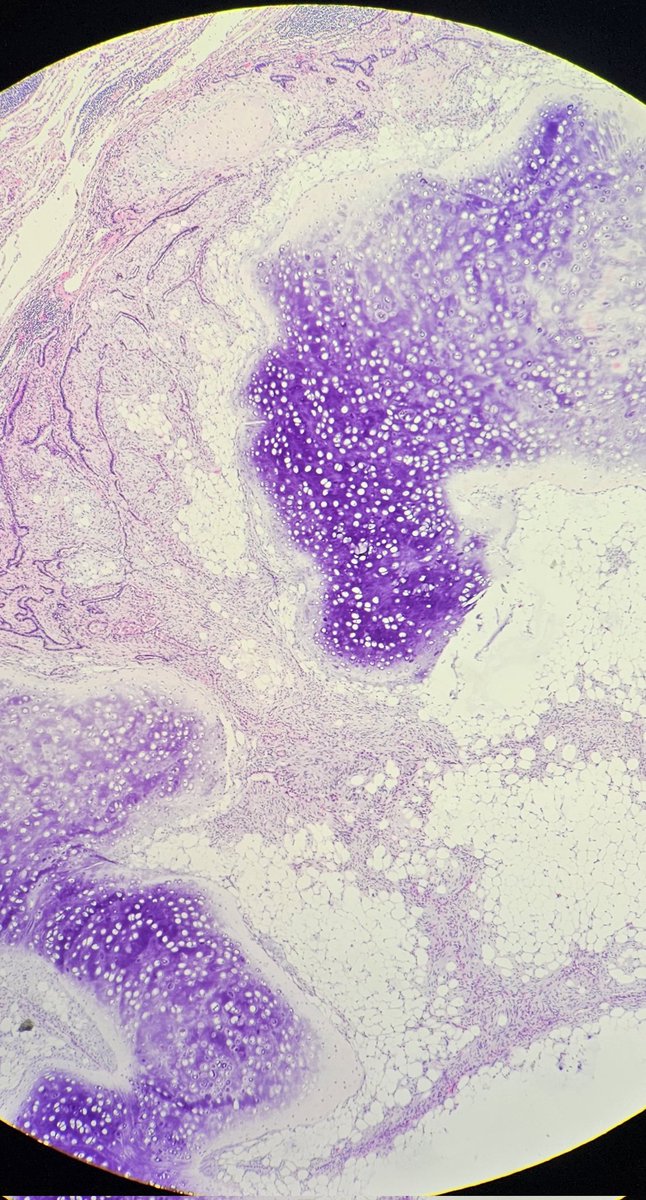

Papillary RCC showing type 1 and type 2 morphologies. #GUpath #pathology